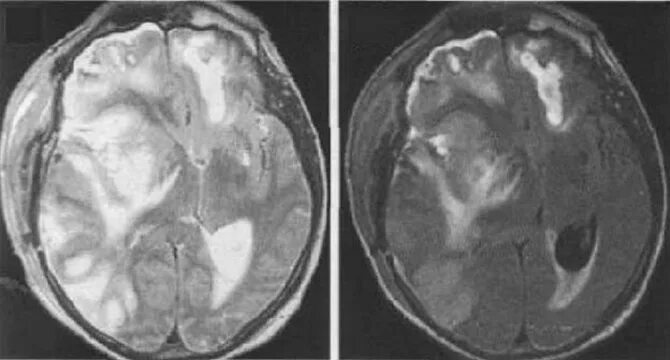

Отек головного мозга операции